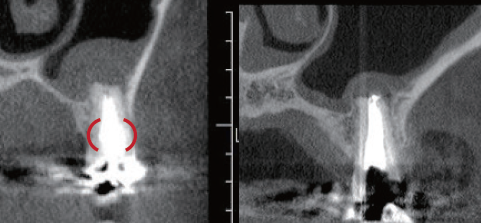

(症例1・①)根管充填の状態は比較的良好である。根管拡大・形成の3次元的評価のためCBCTを撮影。

CT像左上5番根尖部を中心として上顎洞粘膜の肥厚が認められ、根尖性歯周組織炎の影響が上顎洞まで及んでいると考えられた

根管処置後の修復が保存修復されて髄室開拡に制限があり、歯頸部周辺に存在する頬口蓋側に広がる髄角の形態が確認でき(症例1・②)、この部分に根管拡大不足の可能性を疑えた。根尖病変の原因として、頬口蓋的な根管拡大不足による起炎物質の取り残しによる感染が要因の一つであると診断した。より的確な予防形成を行うにあたり、器具操作の向上のため髄室開拡の修正が必要であると判断した。よって最終修復は歯冠修復による補綴修復が必要であると患者に説明し、承諾が得られたので再治療を行なった。

(症例1・②)

線で示した部分に髄角部の形態がそのまま残存していることが予測され拡大不足、未処置部分が存在すると判断した

根管充填後のレントゲン所見を示す(症例1・③)。術前と比較し、レントゲン上では上顎洞粘膜の肥厚も改善傾向が認められる。根尖病変の主原因がバイオフィルムであり、機械的な拡大形成は必須であるため根管を3次元的に捉えて処置することが重要である。デンタルX線では近遠心的な形態は確認することができるが、頬舌的な形態を確認することは偏心投影をしても難しい。CBCTは根管処置を行う上で非常に有益な情報を得ることができると考える(症例1・④、⑤)。

(症例1・④)

術前と比較して頬口蓋方向に膨らんでいた髄角部の形態の変化が確認でき、未処置部分が減少していることが確認できる。上顎洞粘膜の肥厚も術前と比較し改善傾向にある

(症例1・⑤)根尖部のCBCT像

根尖部の開口部は3つ以上存在し、根管充填材が開口部を封鎖していることが確認できる